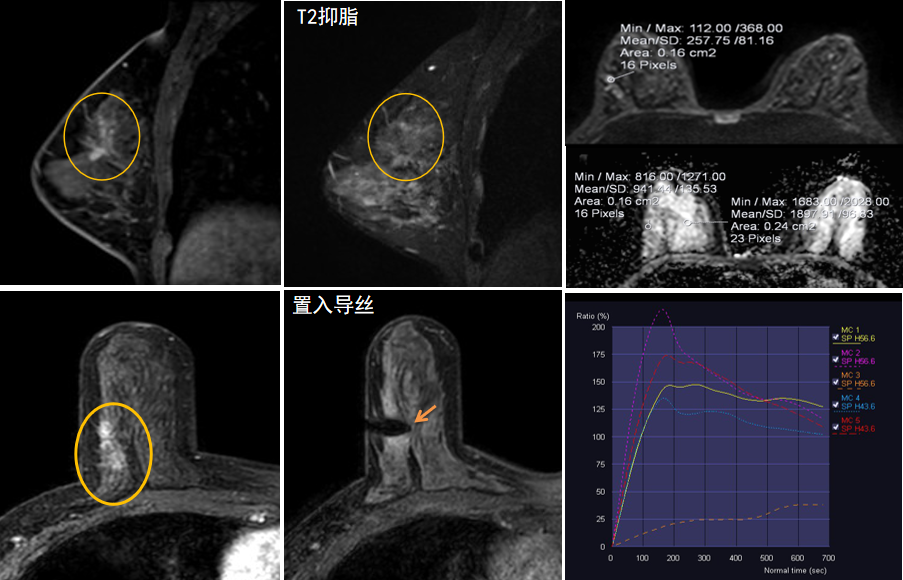

今年45歲的某女士,兩個(gè)月前行超聲檢查發(fā)現(xiàn)右乳結(jié)節(jié),乳腺X線攝影檢查提示右乳外上象限局部腺體結(jié)構(gòu)扭曲并簇狀無定形鈣化,為了進(jìn)一步評(píng)估病變性質(zhì)并確定范圍進(jìn)行了乳腺M(fèi)R平掃 DWI 增強(qiáng)的檢查,經(jīng)MR評(píng)估發(fā)現(xiàn)右乳病變范圍較廣,評(píng)估為BI-RADS 4類可疑病變,需要取得病理學(xué)結(jié)果。

陳寶瑩主任及其帶領(lǐng)的MR介入診療小組詳細(xì)詢問了病情,分析了患者資料,并與患者和臨床醫(yī)生進(jìn)行了充分溝通,確定于手術(shù)前為患者實(shí)施MR引導(dǎo)下的病變穿刺導(dǎo)絲定位和體表范圍確定。手術(shù)前陳寶瑩主任帶領(lǐng)聶品醫(yī)師、馬小偉技師、韓愛萍護(hù)士長(zhǎng)等MR介入診療小組成員,借助MR高清的圖像顯示和定位系統(tǒng),確定病變范圍,精準(zhǔn)穿刺置入定位導(dǎo)絲,并準(zhǔn)確標(biāo)記出病變體表范圍,整個(gè)過程患者無任何不適。在定位導(dǎo)絲和體表范圍標(biāo)記的輔助下,甲乳外科劉曉敏主任精準(zhǔn)切除了病變,解除了患者的后顧之憂。

國(guó)內(nèi)外指南均建議40歲以上的女性每年行一次雙乳X線攝影(鉬靶)檢查,以篩查乳腺癌。對(duì)于乳腺癌高危人群40歲以前即建議開始乳腺癌篩查,除了進(jìn)行乳腺X線攝影(鉬靶)篩查外需要補(bǔ)充MR檢查,MR檢查敏感性最高,能夠發(fā)現(xiàn)大量X線攝影和超聲檢查陰性的可疑病變,基于多模態(tài)、多參數(shù)的結(jié)構(gòu)和功能成像的基礎(chǔ)上,MR能夠精準(zhǔn)顯示病變位置、范圍以及病變內(nèi)的活性區(qū)域,MR引導(dǎo)下的介入診療不但解決了僅在MR顯示的病變的處置難題,而且能夠精準(zhǔn)定位活性區(qū)域,保證了定位、活檢及旋切的準(zhǔn)確性。